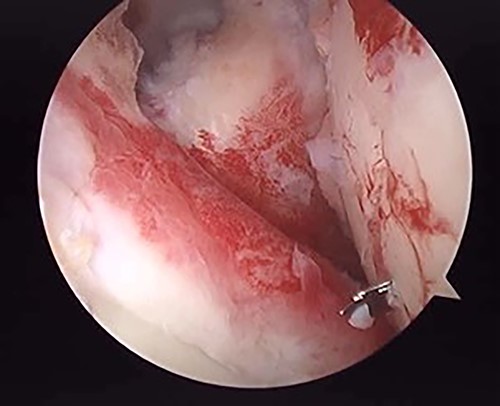

The operation was performed under general anesthesia with an ultrasound-guided brachial plexus block in the beach chair position. First, we performed intra-articular observation by arthroscopy with a 30° scope. Through a posterior portal, we confirmed incongruence of the articular surface of the humeral head, similar to the preoperative findings in 3D-CT (Fig. 4). On the other hand, the posterior joint labrum and glenoid rim were intact. After evaluating the intra-articular lesion, we performed arthroscopic reduction for the impression fracture at the humeral head via the arthroscopic method [5,6]. We split the deltoid muscle and exposed the lateral surface of the humerus. We inserted a Kirschner wire as a reduction guide 2 cm distal from the upper border of the greater tuberosity and 2 cm behind the bicipital groove (Fig. 5). Kirschner wire was inserted to exit the impression lesion while checking the articular surface with an arthroscope (Fig. 6). We created a cortical window (approximately 10 × 10 mm) using a cannulated drill with the Kirschner wire as a guide. To reduce the impression, we pushed the back of the impression using the flat side of the canulated cancellous screw (CCS) drill. After the reduction, artificial bone was inserted from the cortical window to the subchondral bone region to provide support for the depressed area. We then performed a procedure to insert a support screw into the articular surface. The deltopectoral approach was used. First, we dissected the subacromial bursa entirely while visualizing the conjoint tendon. Next, we detached the long head of the biceps at the bicipital groove and sutured it to the pectoralis major muscle. Two CCSs were inserted from the bicipital groove to under the repaired humeral head as support for the reduction site. Finally, after arthroscopic reduction, we performed ORIF for surgical neck fracture using a PHILOS Plate™ (DePuy Synthes).

Posterior arthroscopy of the right shoulder joint. The right is the humeral head side, and the left is the glenoid side. Impression of the humeral head was noted, but the posterior labrum was not damaged.

Posterior arthroscopy of the right shoulder joint showing a reduced depressed surface and the Kirschner wire for reduction guide.